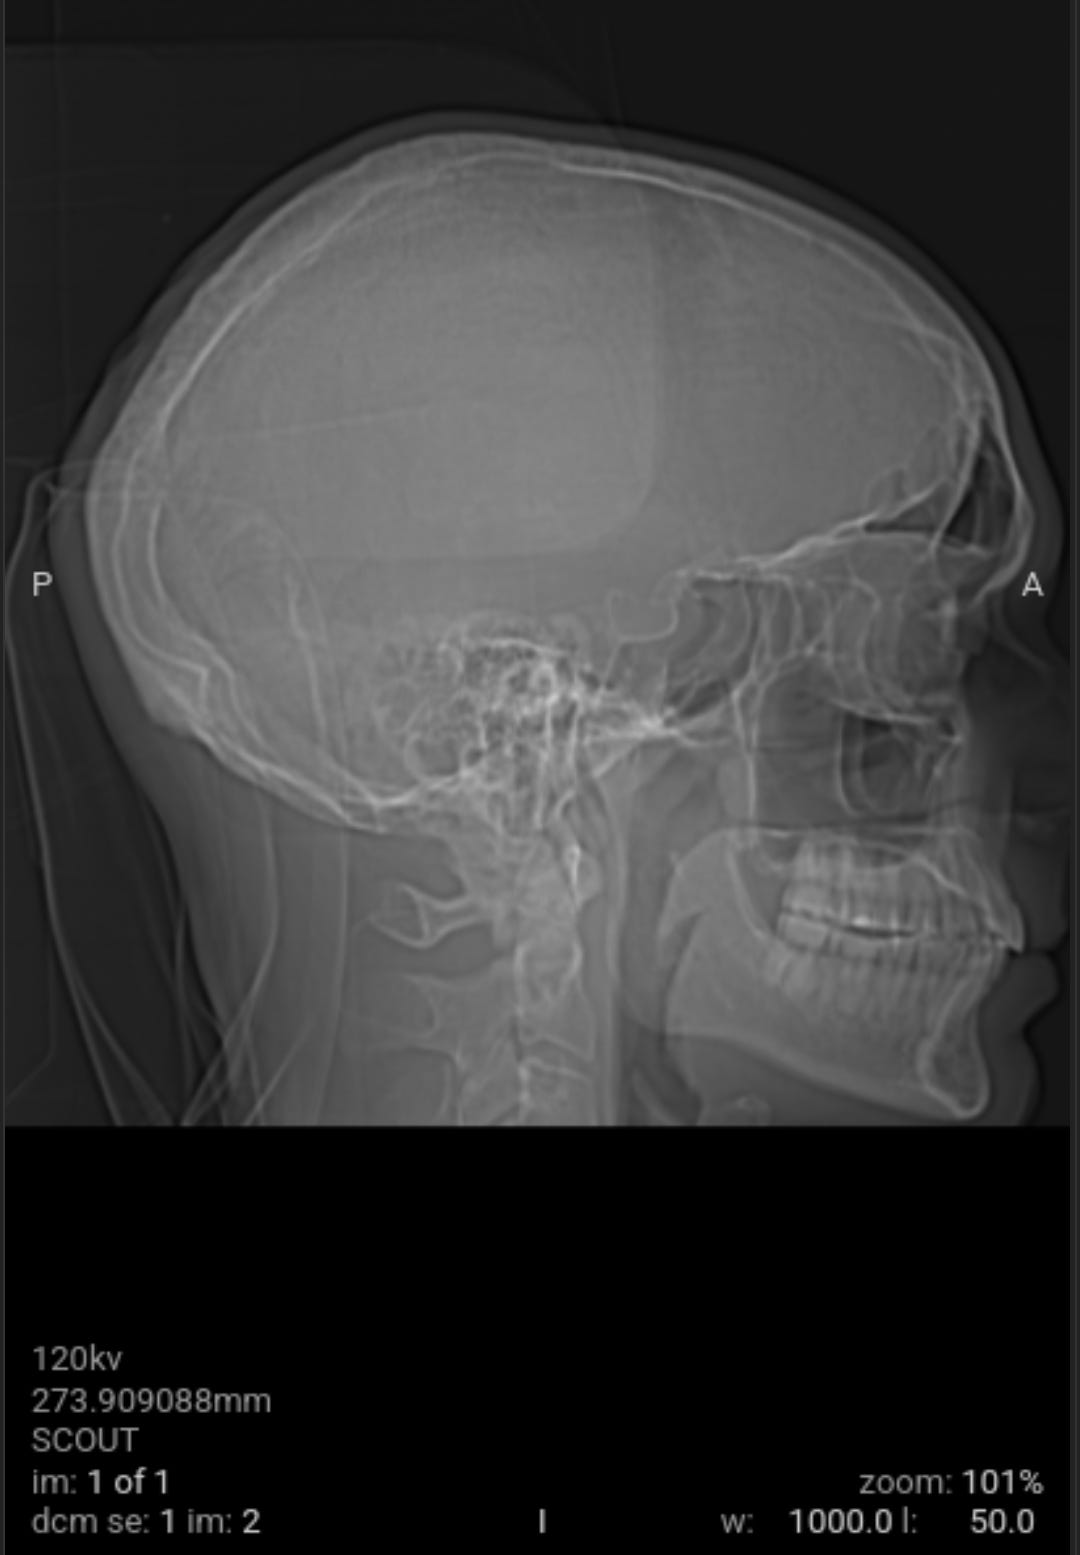

As a followup to eliminate all possible and probably causes of the weaponized audio-video-communications and pathogen nanotechnology. Got blood work and CAT scan done. Results came back good.

As a followup to eliminate all possible and probably causes of the weaponized audio-video-communications CNT and pathogen nanotechnology WPT, I got blood work and CAT scan done yesterday. All came back good with the exception of a low Red Blood Cell RBC count due to my cleansing diet on vegetables and plant based proteins that needs more iron in it with vitamin C, I already dose with vitamin B12 (preference is methylcobalamine). The medical staff could not determine what the unknown material removed from my body was from the salt baths or the material that moved around and itches at times on the left side of my head.

When I had the CAT scan test done, the free electron cascade reaction silenced the CNT local subnet. Anyone who has electronic harassment should know that this is the second time that I have confirmed a free electron cascade reaction destroys the circuitry that is programmed from your prior local environment LOTL CNT and global CNT as well as any mass transfer based CNT subnets. The first time I confirmed CAT scan quenched CNT by free electron cascade reaction was in late 2022 and now again in 2025 (although all of the work done from 2022 through today has significantly reduce the CNT junk, to nearly undetectable levels).

The void spaces on left side are what I suspect to be where the nanotechnology circuitry was removed by magnetic vortex skyrmion unit, chelators, salt water baths, no yeast diet and no added sugar diet. Note the scans do not show any nanotechnology based synthetic biology parasites. This is why the samples pulled from my body were classified as unknown by the western medical staff not trained in the nanotechnology and synthetic biology knowledge domain, a huge gap in Western medicine.